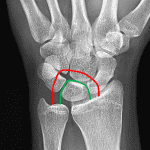

- Acute lunate dislocation with 90 degrees volar tilt and 1 cm volar displacement of the lunate

- Tiny ossific densities project along the dorsal aspect of the proximal carpal row

- Lunate dislocation

Acute lunate dislocation with 90 degrees volar tilt and 1 cm volar displacement of the lunate.

Tiny ossific densities project along the dorsal aspect of the proximal carpal row, which may represent tiny chip/avulsion fractures. No additional fracture identified.